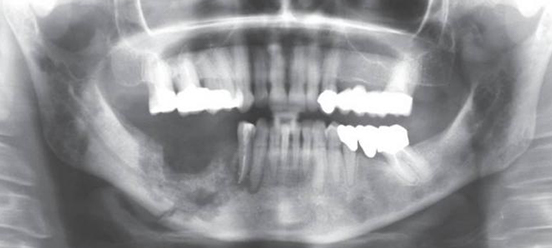

There are two separate issues, discovery, and diagnosis. Discovery is the result of a thorough visual and manual examination. A protocol for a comprehensive oral cancer screening appears elsewhere in this section of the web site. It includes a systematic visual examination of all the soft tissues of the mouth, including the manual extension of the tongue to examine its base, a bimanual palpation of the floor of the mouth, and a digital examination of the borders of the tongue, and the lymph nodes surrounding the oral cavity and in the neck. New diagnostic aids, including lights, dyes, and other techniques are beginning to appear in the marketplace. While potentially making the discovery process more effective, it is still possible to do a comprehensive examination through a proper visual and tactile process without adjunctive devices.